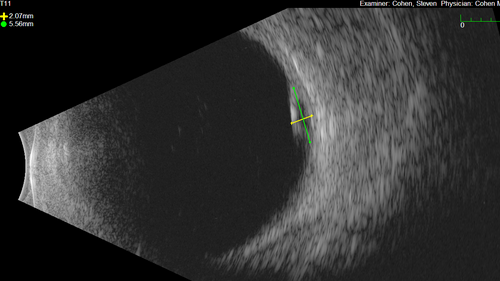

Serous Macular Detachment from Small Choroidal Melanoma

72 year old female misdiagnosed as CSR who had small choroidal melanoms.